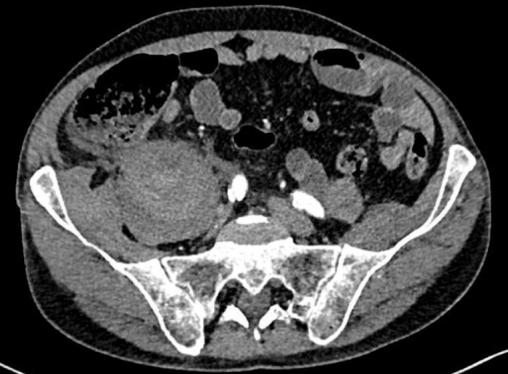

Hématome du psoas

2. Hématome du psoas